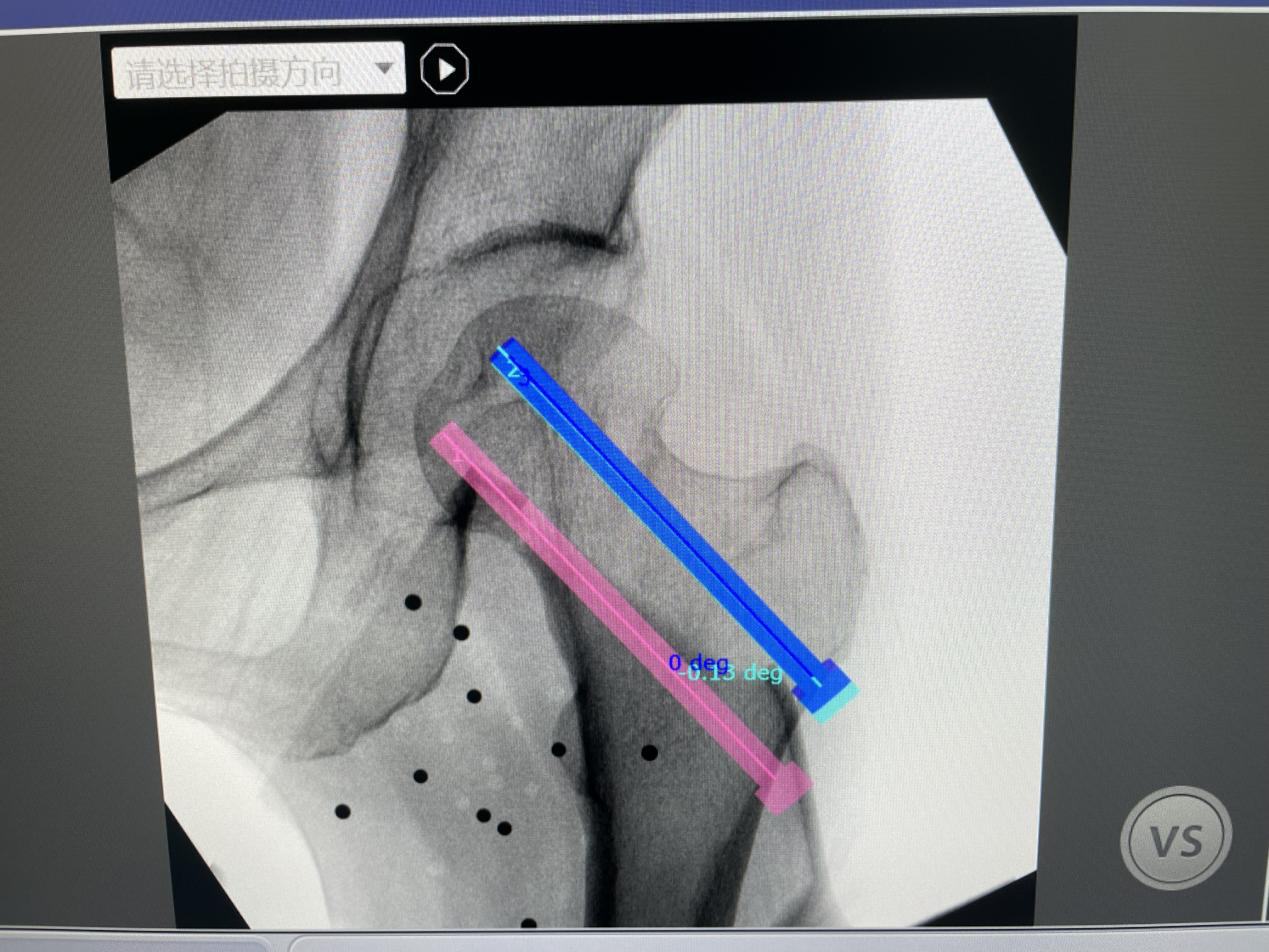

骨科手术机器人由机械臂和仿真手组成,是骨科手术精准导航的利器,又被称为“独臂侠”,正越来越成为骨科医生的好帮手。手术中,仅需3-5次X光透视,就可以在电脑上重建出股骨颈的三维形态和螺钉位置规划,通过红外线探测,准确识别出患者需要置入螺钉的方位。随后,机械手臂会根据系统指令运行到指定的置入点,医生只需要打入导针,即可成功置入螺钉。股骨颈骨折对固定螺钉的位置及分布要求高,与术后固定的强度及骨折愈合密切相关,通过机器人规划及导航能精准且一次成功做到三枚螺钉平行、贴边、倒三角形分布

系统显示的预测置入螺钉方位模拟图